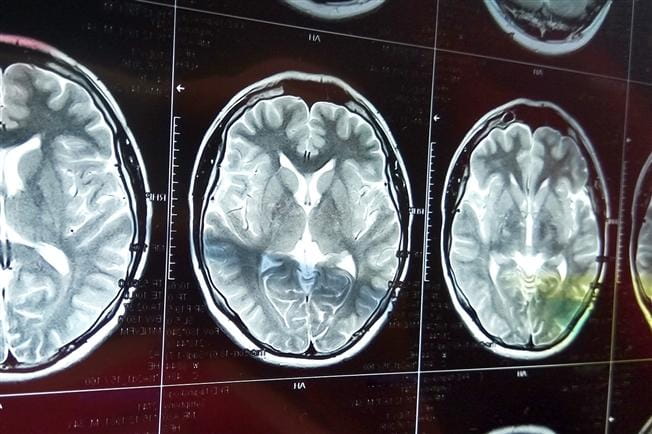

A stroke can be caused by blockages and bleeding.

Most strokes (87%) are caused by a blockage — or clot — in a blood vessel in the brain, which blocks blood flow to the brain and deprives it of oxygen. Strokes can also be caused by bleeding in the brain caused by an aneurysm or other condition.

Millions of brain cells are lost every minute during a stroke. It is critical to get advanced medical care as quickly as possible. Call 911 immediately.

With the most sophisticated imaging equipment available, we can quickly diagnose and provide life-saving treatments such as intra-arterial tPA, endovascular coiling, angioplasty and stenting. At Main Line Health, we’re committed to bringing the most advanced medical services to our patients, and our neurointervention lab is just one example of this dedication.